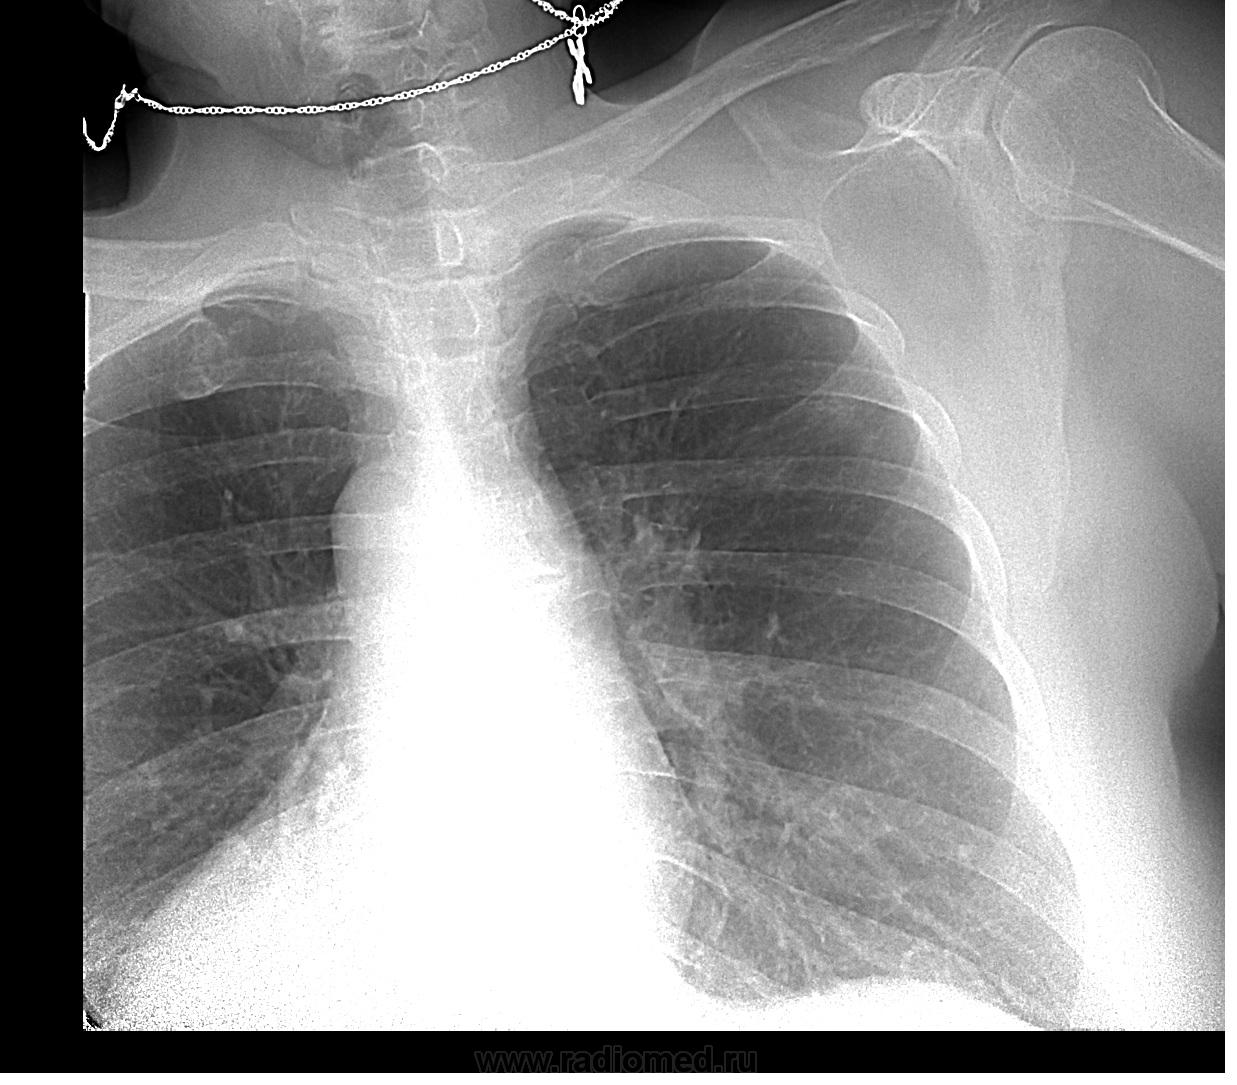

Получается что так Ну и еще скорее всего была пневмония в правом легком, поэтому образовались плевро-диафрагмальные спайки, ничего подозрительного не вижу.

Диафрагма в 3-м межреберье справа?))))...присмотритесь...там субплевральный очаг...

В верхней доле правого лёгкого с самого начала очаг НЕ один был. Через год появился инфильтрат субплеврально и за первым ребром неспокойно. Ещё и слева очаги вероятны

Сухой (фибринозный) плеврит справа+плевро-диафрагмальные изменения справа+единичные очаги: tbc? саркоидоз?

а вот меня весь кортикальный слой в/доли правого легкого смущает...

В 3м межреберье действительно очажок, похожий на онкологический

Вот правильный ответ! Похоже при "бронхите", что-то с правым синусом. А плюс какая-то мелочь справа на верхушке?